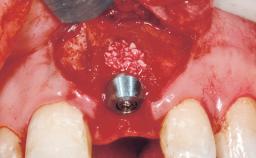

Immediate Flapless Placement of an Implant in a Maxillary Left Central Incisor Site

A 42-year-old female patient was referred to our clinic at the School of Dentistry of the University of São Paulo in November 2004, presenting a deficient restoration in the upper left central incisor. The clinical examination revealed no gingival retraction or any signs of gingival inflammation and, therefore, previous periodontal treatment was not considered. The patient presented a high lip line at full smile and a thin tissue biotype. This combination characterized a high-risk situation from an anatomic point of view, which required careful preoperative planning and cautious surgical execution.